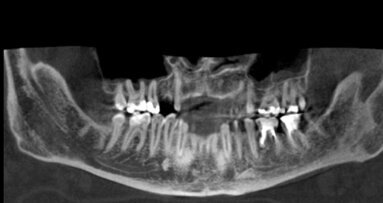

Dwudzielny kanał żuchwy jest anatomiczną odmianą budowy kanału żuchwy oznaczającą, że kanał żuchwy jest podzielony na dwie gałęzie. W ...